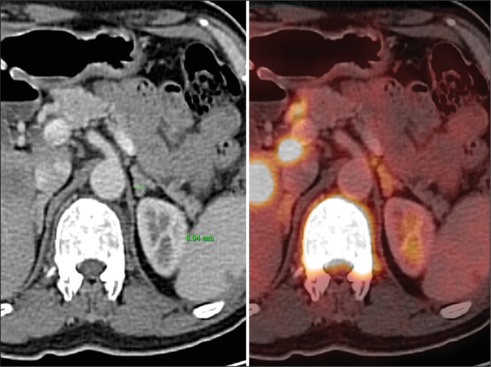

Detection of adrenal lesions either incidentally, or in symptomatic cases and/or during staging/restaging of oncological cases, it is very crucial to know the adrenal lesion is benign or malignant. Fluorodeoxyglucose positron emission tomography-computed tomography (FDG PET/CT) helps in this comprehensive evaluating process. Here, we present the most frequently facing adrenal lesions in routine oncological PET/CT scans. The aim of this presentation is to know the FDG uptake spectrum of various adrenal lesions on PET/CT scan so that increase the diagnostic accuracy and spectrum of differential diagnosis.

Abstract Image